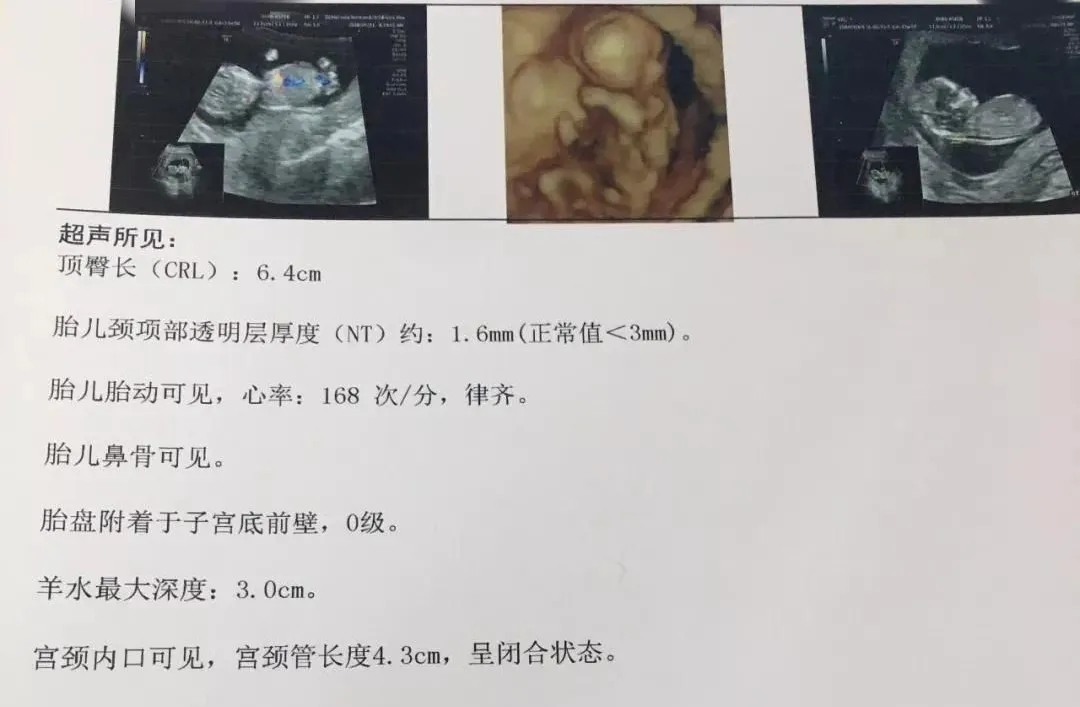

NT是胎儿颈部半透明膜的缩写,是10~13孕周围绕在胎儿颈项后部流动性的半透明蛋白膜。它的厚度与胎儿DS缺陷正相关,并可以通过超声成像测量。NT检查便于及早发现唐氏儿、先天性心脏病和其他结构畸形的胎儿,并及时予以干预。

报告中NT的数值含义

NT增厚越明显,胎儿异常机会就越高,异常程度也会越严重。一般正常的NT厚度不能大于3mm,当大于3mm时约10%会发育为异常胎儿;当大于6mm时,这个异常程度会大大增加,约90%会发育成异常胎儿。